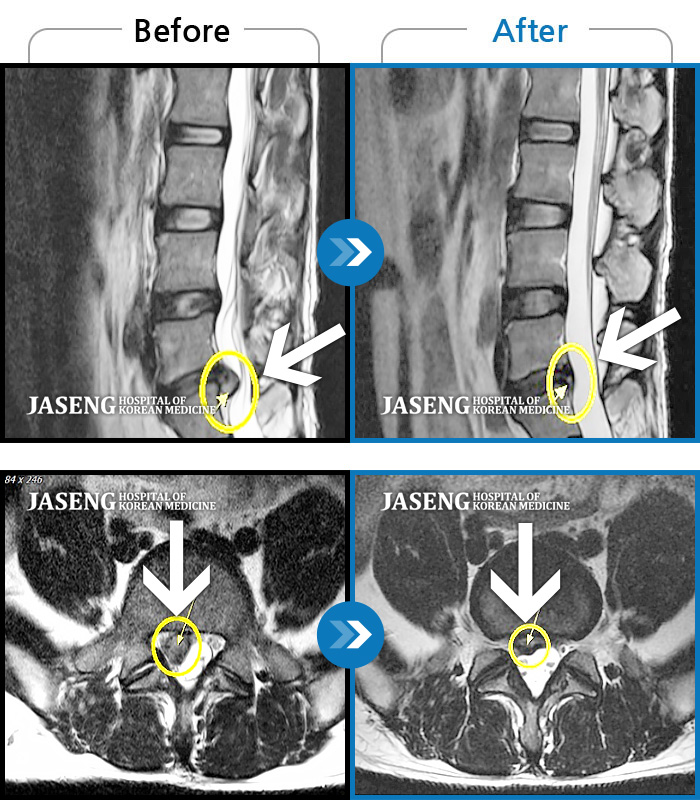

Before

After

환자에게 사전 동의를 받아 동일 조건에서 촬영되었습니다.

개인에 따라 치료 후 부작용이 발생할 수 있으니 의료진과 상담 후 치료를 진행하시기 바랍니다.

허리 양측 둔부에서 발가락으로 통증, 비증, 힘이 빠지는 증상

허리 양측 골반에서 좌측 발가락까지 통증, 저림 증상